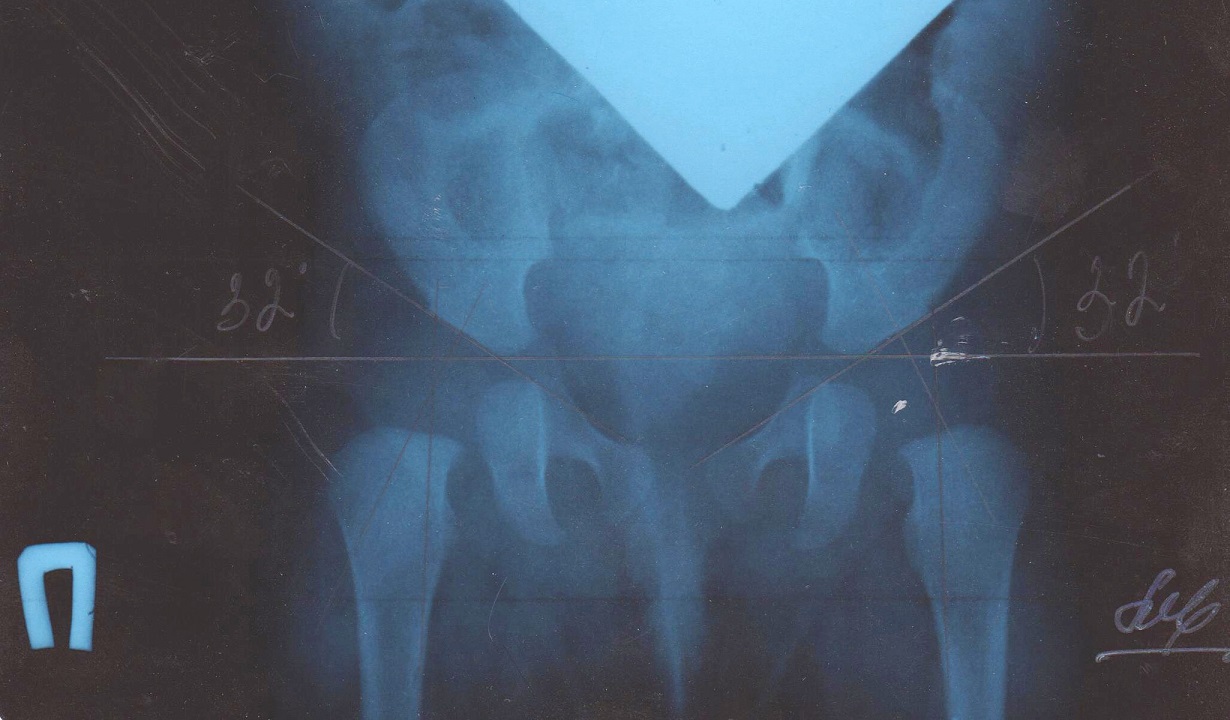

Рентген ТБС: Нормальные показатели

Раздел: Необычные решения